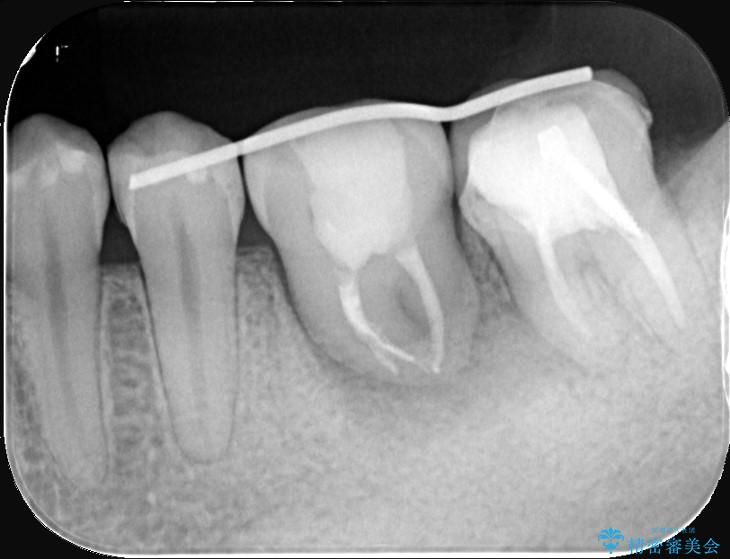

保存が難しい左下6番目の歯を抜歯し、左下8番目の歯(親知らず)を抜歯窩に移植しました。歯牙移植後の動揺防止のため暫間固定を行っています。

また移植後2週間経過時点で根管処置が必要となります。

骨との定着を確認し、今後矯正治療を行う予定のためレジン冠をセットしています。